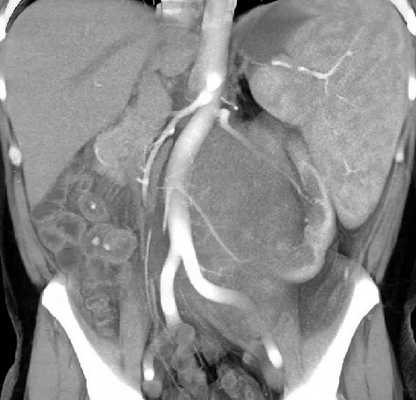

Компьютерная томография брюшной полости и забрюшинного пространства

Компьютерная томография более детально дает информацию об анатомическом отношении опухоли к окружающим тканям и органам, позволяет оценить структуру опухоли (рис. 5).

Рис. 5. КТ нейрогенного образования забрюшинного пространства справа